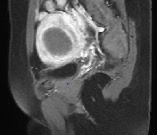

Imaging Outcomes

Figure 4. (A-D). Contrast-enhanced MRI obtained from a 35-year old patient with uterine fibroid. (A). Pre-HIFU MRI showed a significant enhancement of a uterine fibroid located at the anterior wall of the uterus, and the size of the fibroid was 5.6 cm x 4.6 cm x 4.9 cm; (B).1-day post-HIFU MRI showed no enhancement of the treated fibroid, the uterine fibroid was completely ablated; (C). 4-month post HIFU MRI showed the size of the treated fibroid reduced to 5.0 cm x 4.3 cm x 4.2cm, the shrinkage was 28.5%; (D). 10-month post-HIFU MRI showed the size of the treated fibroid reduced to 3.5 cm x 3.0 cm x 3.2cm, and the shrinkage was 73.4% compared to baseline. Images courtesy Prof. Zhang Lien.